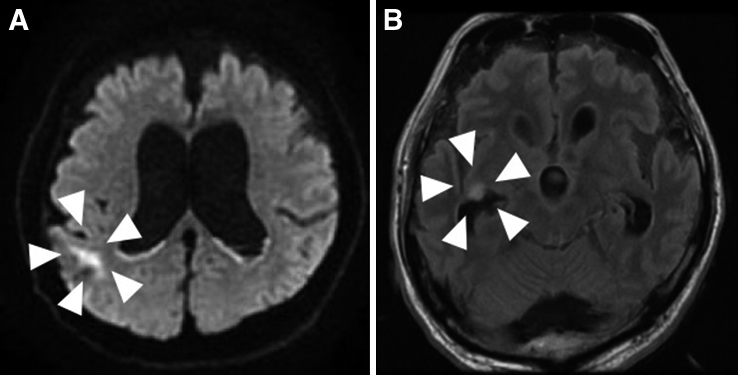

術後38°C以上の発熱が遷延し,炎症反応も高値であった.第3病日からは意識障害を認めた.第7病日には血液培養陽性(Enterococcus faecium),SOFA scoreは8点となり敗血症性播種性血管内凝固症候群(disseminated intravascular coagulation;以下,DICと略記)と診断した.CTでは肺炎像を認めるのみであり(Fig. 3),その他に縫合不全や腹腔内膿瘍といった腹腔内感染を示唆する所見を認めなかった.また,心臓超音波検査で感染性心内膜炎は否定的であった.これらの結果から術後肺炎による敗血症性DICと診断した.喀痰培養検査ではKlebsiella pneumoniae,Enterobacter aerogenes,Pseudomonas aeruginosaなどが検出され,薬剤感受性試験の結果に基づき予防的抗菌薬として投与していたセフメタゾール(CMZ)からメロペネム(meropenem;以下,MEPMと略記)+バンコマイシン(vancomycin;以下,VCMと略記)に変更した.その結果,炎症反応は改善傾向を示したが,発熱と意識障害は依然として遷延していたため薬剤熱の可能性を鑑みてICT(Infectious Control Team)とも協議の結果,VCMをテイコプラニン(teicoplanin;以下,TEICと略記)に変更した.血液検査では電解質やホルモン値などは正常範囲内であり,低Na血症や甲状腺機能低下症といった意識障害の原因となりうる疾患の存在は否定的であった.薬剤熱や悪性症候群などが疑われ,被疑薬の中止・変更,ダントロレン投与を行ったが,発熱と意識障害は改善しなかった.さまざまな検査にもかかわらず熱源の診断に至ることができず,一般的な術後管理の範疇を超える病態と考えられたため神経内科コンサルトを行い,UCに合併するIgG4関連肥厚性硬膜炎や易感染性に伴う細菌性・真菌性髄膜炎が鑑別診断として挙げられた.しかしながら,Kernig徴候や項部硬直などの神経学的所見に乏しく,第50病日に施行した頭部CT所見でもこれらの疾患を示唆する髄膜・辺縁系・基底膜の造影効果増強といった有意な所見は得られず,診断に至ることはできなかった(Fig. 4).第63病日からKernig徴候と項部硬直が顕在化し,頭部MRI拡散強調像で脳室内高信号を認め,髄膜炎が熱源であることが示唆された(Fig. 5).髄液検査においても蛋白の上昇と糖の低下を認め,さらに,髄液培養検査でEnterococcus faeciumを検出し,最終的に細菌性髄膜炎の診断に至った.髄液培養検査と感受性試験の結果を考慮し,抗菌薬をタゾバクタム/ピペラシリン(TAZ/PIPC)からMEPMとVCMに変更し,約6週間継続したところ,発熱と意識障害は改善した.その後施行した髄液培養検査にて細菌培養は陰性化し,頭部MRIで髄膜炎を示唆する脳室内高信号所見の消失を確認し,細菌性髄膜炎は治癒したと診断した.

Head MRI performed 63 days after the surgery using diffusion weighted imaging revealed high signals in the ependyma and intraventricular region (A). Leptomeningeal high signal confirmed in FLAIR imaging indicated meningitis (B).